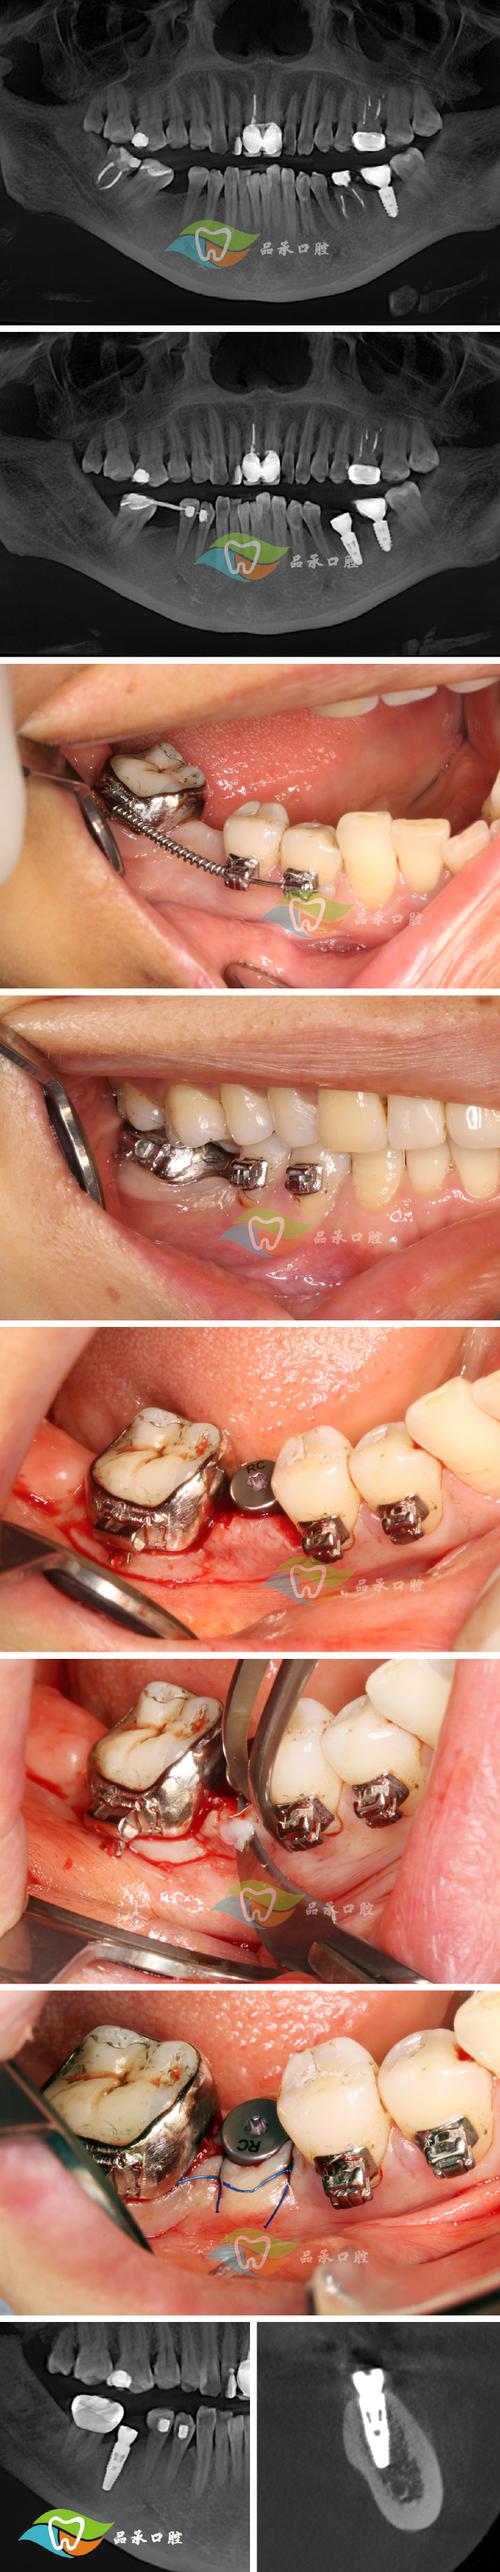

(图片来源网络,侵删) -

托槽或颊面管的影响:

如果问号钩是焊接在颊面管(后牙上的金属管)上,或者靠近托槽,其位置可能受到这些部件的限制,更容易压迫牙龈。